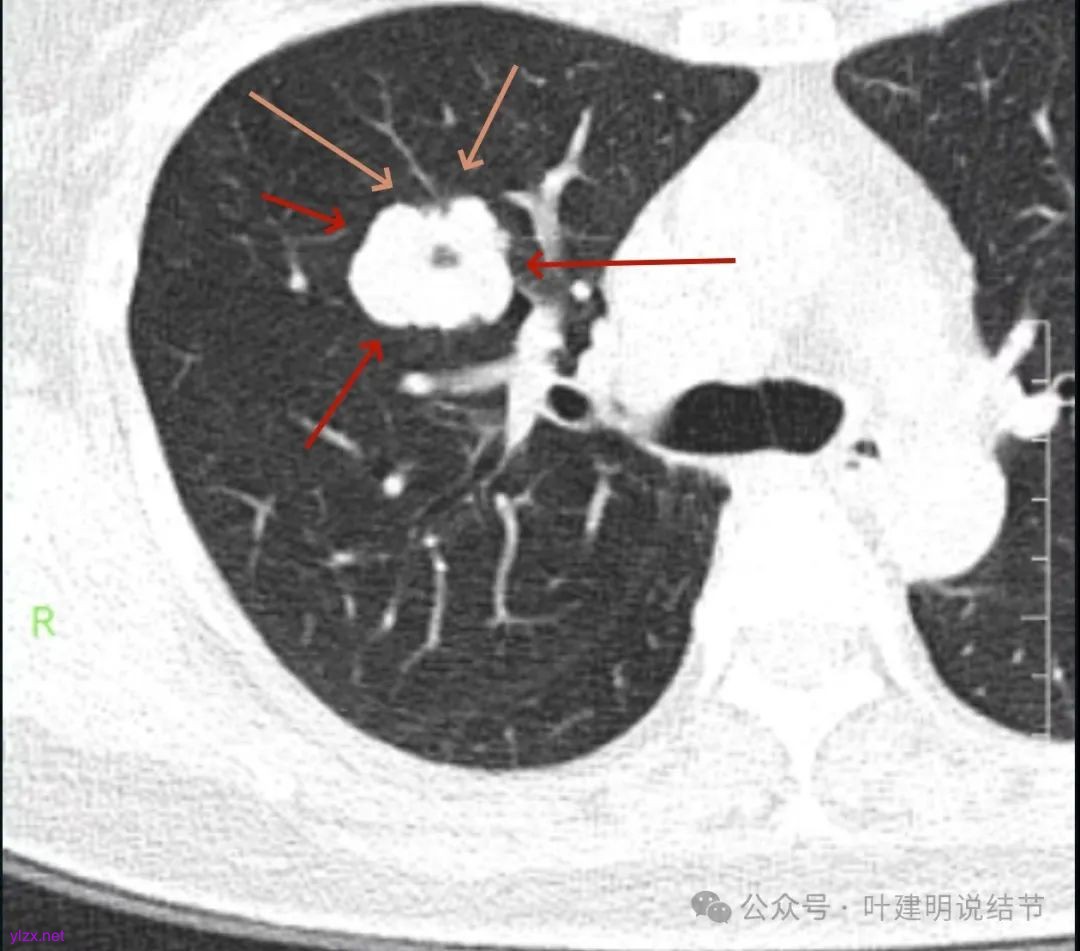

咳嗽近三周,CT检查提示右肺上叶空洞病变。

影像展示与分析:

腔静脉旁明显肿大淋巴结。

你的右上叶这个病灶基本上肯定是肺癌,要尽快处理。从影像上看有以下特点:1、整体轮廓清楚,不似普通炎症的周围有晕或阻塞性改变;2、边缘明显的浅分叶,总体上的感觉膨胀性明显,不管哪个层面看上去都是鼓鼓的;3、边缘区域有磨玻璃成分而且也是分叶状的;4、部分层面见血管进入;5、空腔病灶的壁厚薄不均,内壁不光滑。我考虑中低分化肺癌,由于腔静脉旁有明显肿大淋巴结,需要进一步完善增强CT以及PET-CT检查以明确有无远处转移,是否仍可手术治疗(从病灶本身来说是可以肺叶切除治疗的)。要尽快处理。意见供参考!